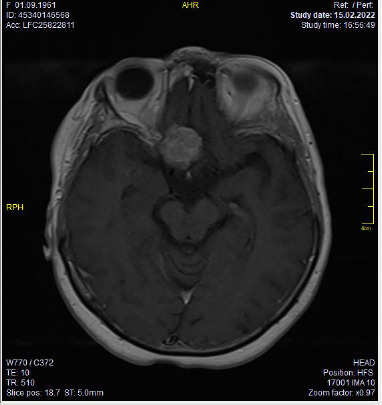

Methods: In this case report, a 62-year-old patient presented to our clinic with sudden visual loss in the right eye and underwent ophthalmological examination. Visual field (VF), retinal nerve fibre layer (RNFL) thickness test, and contrast-enhanced cranial and orbital magnetic resonance imaging (MRI) were performed. The patient was diagnosed with OGM compressing the optic chiasm and nerve, and was operated on by the neurosurgery department. Post-operative examinations were repeated, and the patient was followed up regularly.

Results: Evaluations revealed a significant improvement in the patient's visual functions, including visual acuity and visual field (VF). Postoperative RNFL-thickness tests showed minimum variation. Early surgical treatment of OGMs compressing the optic chiasm and the optic nerve resulted in significant improvements in visual acuity and visual field (VF).